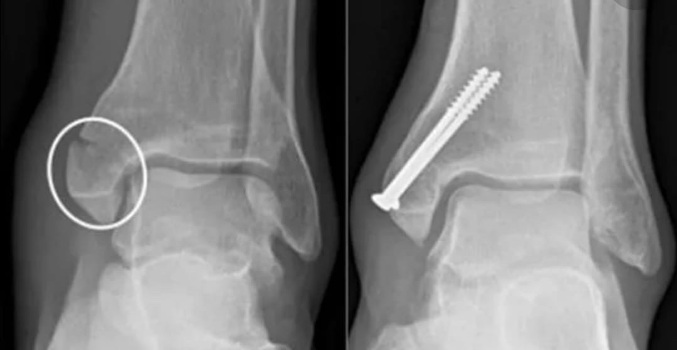

ОСТЕОСИНТЕЗ - это хирургический метод лечения переломов костей, при котором костные отломки фиксируются друг с другом при помощи специальных металлических конструкций (спицы, винты, штифты, гвозди).

Вид металлоконструкции и способ её установки подбираются врачом травматологом-ортопедом индивидуально.